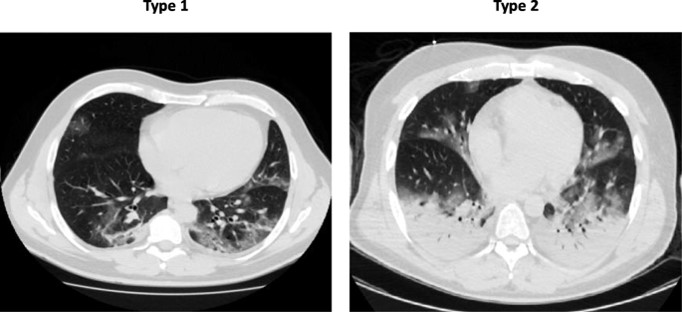

Описаны два принципиально разных варианта повреждения легких при COVID-19 по мнению Luciano Gattinoni и соавторов (Critical Care, апрель 2020).Подробнее

Первый тип с минимальным невентилируемым объемом легких (около 8% на снимке слева) и некритично сниженным комплаенсом выглядит как нарушение перфузии вызванное дисбалансом легочного кровотока и развивается у большинства пациентов. Второй тип, на снимке справа, это 20-30% пациентов, которые поступают с уменьшенным объемом легких (на данной картинке справа он меньше почти в двое), резко сниженным комплаенсом, характерным для тяжелого острого респираторного дистресс синдрома (ОРДС). Комплаенс легких и грудной стенки, способность к растяжению легких в ответ на давление является ключевым параметром в определении ОРДС, определяет прогноз и тактику ведения пациента. Именно по этой причине у таких пациентов в дополнение к пневмонии нередко наблюдается повреждение легких вызванное собственно ИВЛ. Таким образом, несколько игнорируя Берлинские критерии, авторы считают, что у 70-80% пациентов заболевание проходит без ОРДС, а тяжесть гипоксемия не соответствует механическим параметрам работы легких.